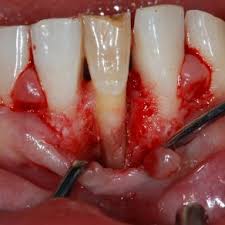

Cemental tears have been reported as periodontal breakdown associated with separation of the cementum from the remaining tooth structure. • trauma may be considered as a potential aetiologic factor for cemental tears in addition to occlusal traumatism and aging. Cemental tear represents a rare form of root surface fracture which makes teeth prone to periodontal breakdown. This case report presents macroscopy, light microscopy (lm), and scanning electron microscopy (sem) observations of fragments of cet. The occlusal surface of the first premolar showed no caries while the second premolar was covered with a. In one specimen, the cemental tear fragment was partially attached to the root after the extraction procedure. Cemental tear is defined as cementum fragment completely or partially detached from the root surface, and it has been associated with localized rapid periodontal breakdown. However, to the best of the authors' knowledge, cases of cemental tears in autotransplanted teeth and their recovery by autotransplantation have not been reported previously. Cemental tears have been described as specific types of root surface fractures that are seen infrequently but can cause rapid collapse of the periodontal tissue. This leads to difficulty in the early diagnosis of cemental tears. A cemental tear (cet) is a special type of surface root fracture that may cause periodontal and even periapical tissue destruction. The phenomenon is believed to be elicited by overloading or acute trauma from occlusion. Case reports of cemental tears have been associated with age, trauma, and traumatic occlusion.

Cemental tears have been described as specific types of root surface fractures that are seen infrequently but can cause rapid collapse of the periodontal tissue. A cemental tear is a specific type of root surface fracture infrequently seen in clinical dental practice 1, 2. Cemental tear surfaces demonstrated a significantly greater loss of attachment than opposite intact surfaces (p < 0.0001). It can lead to rapid periodontal breakdown, and recently not many reports have focused on periodontal concerns. The increasing probing depth associated with a cemental tear seems to indicate that this phenomenon contributed to loss of attachment and bone. This specimen was processed for light microscopy to determine the location of the cemental tear fracture. The mechanism by which cemental tears develop is currently unknown, but several etiological factors have been reported including age, traumatic occlusion or a traumatic event (7, 8). Cemental tears often show characteristics mimicking a periapical or periodontal lesion. Cemental tear represents a rare form of root surface fracture which makes teeth prone to periodontal breakdown. Cemental tears have been rarely reported in the endodontic literature. Although history of trauma and/or attrition may be risk factors, the etiopathology of cemental tear remains unknown. Case reports of cemental tears have been associated with age, trauma, and traumatic occlusion. Etiologic factors that lead to tearing of cementum are not known, but most frequently suggested causes are excessive occlusal force, previous trauma history, and aging.

There are few common clinical features that could suggest the presence of cemental. Cemental tear surfaces demonstrated a significantly greater loss of attachment than opposite intact surfaces (p < 0.0001). Cemental tear is a clinical term referring to partial or complete separation of the cementum from the root surface. Cemental tears have been rarely reported in the endodontic literature. Aim to report a case of a cemental tear. Aging, trauma and occlusal overload are the main aetiological factors. However, to the best of the authors' knowledge, cases of cemental tears in autotransplanted teeth and their recovery by autotransplantation have not been reported previously. An exploratory surgery, extraction, and biopsy resulted in a diagnosis of cemental tear.

With the increasing age of the dental population and longer retention of teeth, clinicians should be aware of this rare entity. The occlusal surface of the first premolar showed no caries while the second premolar was covered with a. Key learning points • the detachment of a fragment of cementum is described as a cemental tear. Cemental tears often show characteristics mimicking a periapical or periodontal lesion. Cemental tears are more common in the middle (45.3%) and apical third (41.5%) of the root. This specimen was processed for light microscopy to determine the location of the cemental tear fracture. Cemental tear surfaces demonstrated a significantly greater loss of attachment than opposite intact surfaces (p < 0.0001). Shop quality handcrafted cement tiles. It can lead to rapid periodontal breakdown, and recently not many reports have focused on periodontal concerns. The mechanism by which cemental tears develop is currently unknown, but several etiological factors have been reported including age, traumatic occlusion or a traumatic event (7, 8). Case reports of cemental tears have been associated with age, trauma, and traumatic occlusion. Etiologic factors that lead to tearing of cementum are not known, but most frequently suggested causes are excessive occlusal force, previous trauma history, and aging. In this case report, three teeth with complete or incomplete cemental tear in two patients were presented.